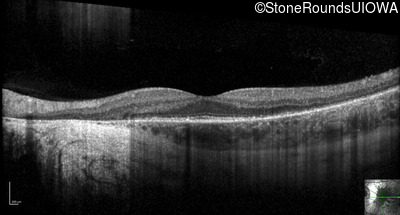

Optical Coherence Tomography - Left - 20/16

Exemplar / OCT Stack